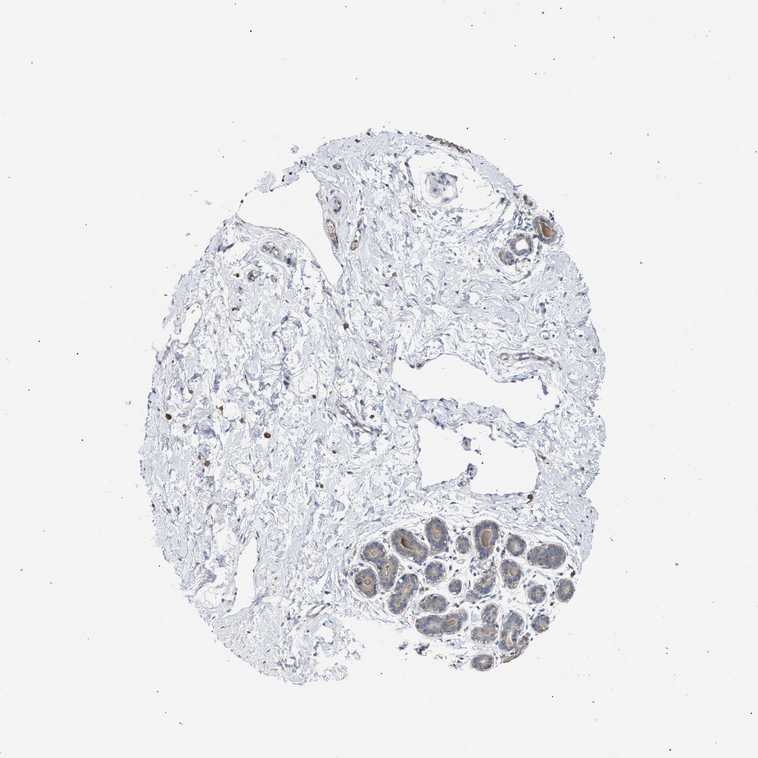

BREAST - Antibody stainingi

Antibody staining in the annotated cell types in the current human tissue is reported as not detected, low, medium, or high, based on conventional immunohistochemistry profiling in selected tissues. This score is based on the combination of the staining intensity and fraction of stained cells.

Each image is clickable and will lead to virtual microscopy that enables deeper exploration of all samples and also displays staining intensity scores, fraction scores and subcellular localization as well as patient and tissue information for each sample.

Antibody HPA017885

Adipocytes Not detected

Glandular cells Low

Myoepithelial cells Low